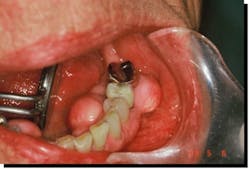

This unique loss of tooth structure (noncarious lesions, NCLs) has been the subject of controversy among dentists for almost 100 years (figure 1). W I Ferrier (1931) once remarked, “Their etiology seems to be shrouded in mystery.”8 We now understand that these multishaped deformations are examples of hard tissue fatigue due to compression failure. Fatigue, a weakened state brought about by repeated stressing, is one of the most insidious causes of loss of strength in a structure.9

Fatigue factors did not come into recognition until the introduction of rotating metal machinery in the middle of the nineteenth century. In time with the emerging science of biomechanics, dentists began to recognize their significance in the study of the mechanical behavior of living materials.10 Minute particles of tooth structure are being shed at vulnerable sites of high stress. The cuspid in figure 1 demonstrates changing sites of failure as alveolar bone recedes.